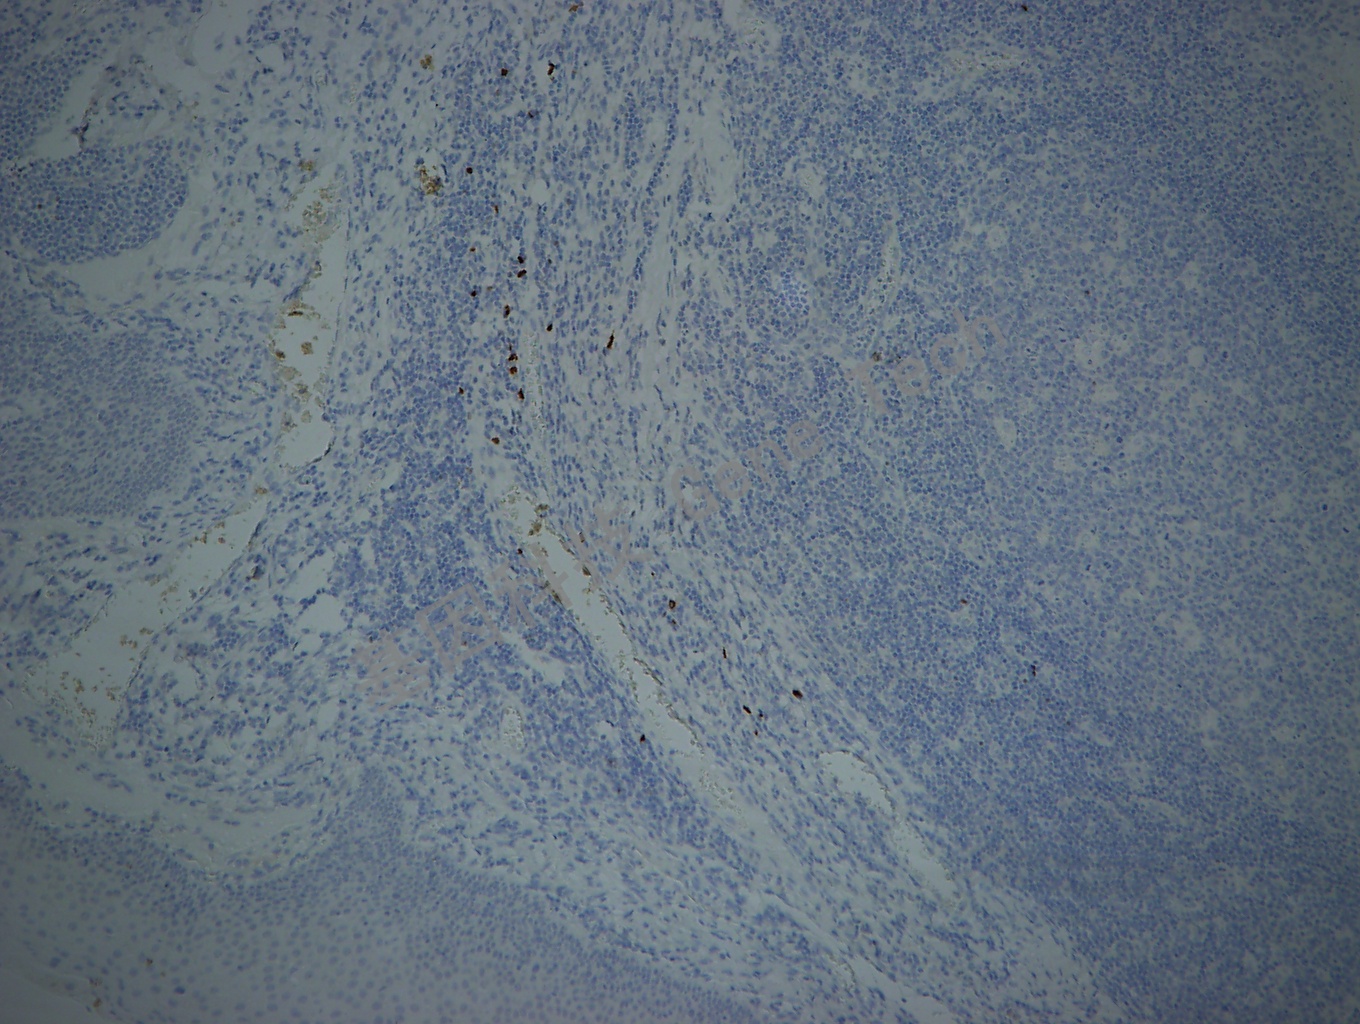

胸腺石蜡切片,用 TdT(GT2025)染色,细胞核阳性,DAB 显色。